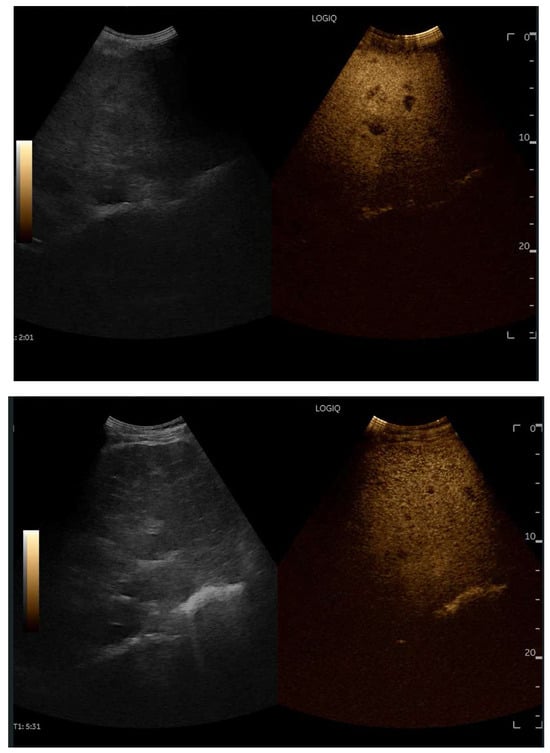

CEUS is valuable for characterizing the contrast enhancement patterns of liver nodules [68,69,70,71]. In Europe, the US contrast agent SonoVue® (sulfur hexafluoride; Bracco, Milan, Italy) is approved only for intravenous applications in patients over 18 years of age [72]. CEUS use in Fontan patients remains limited due to their frequent collateral circulation with right-to-left shunts, which is considered a contraindication in Europe but not in the United States. Beyond structural liver changes, CEUS reveals markedly heterogeneous hepatic enhancement with mosaic or reticular patterns, mainly due to slow and reduced enhancement near congested hepatic veins—one of the most common imaging features of FALD [54,73]. Anecdotal experience suggests that CEUS demonstrates heterogeneous and decreased liver enhancement in the portal venous phase, similar to cirrhosis of other etiologies (Figure 14, Figure 15). Abnormal enhancement is more prominent at the liver periphery than centrally, while the hypertrophic caudate lobe often shows more homogeneous enhancement. In patients with FALD, the altered hemodynamics resulting from chronic hepatic venous congestion and low cardiac output can significantly influence CEUS dynamics. Despite these circulatory changes, CEUS in FALD generally preserves the standard temporal enhancement pattern. The hepatic veins, although congested, do not typically show early enhancement, as microbubble distribution primarily reflects arterial input. The systemic hypokinetic circulation characteristic of FALD may lead to delayed arterial arrival times and a prolonged transit of contrast, especially in the background of the liver. Nonetheless, FNH-like nodules frequently exhibit intense and early arterial-phase hyperenhancement, suggesting preserved or increased arterial supply in these lesions. This contrast behavior is essential for lesion characterization.

Figure 14.

Contrast-enhanced ultrasound (CEUS) in the late phase shows the appearance of hypo-vascular areas due to varying degrees of congestion and hepatic alteration. These areas may mimic malignant nodular lesions with early washout.

Figure 15.

CEUS exam showing late heterogeneous enhancement in the arterial phase with evidence of hypo-enhanced areas, thus mimicking a malignant wash-out.

CEUS plays a crucial role in evaluating hepatic nodules in FALD and Figure 16 (Figure 17). In non-cardiac cirrhosis, contrast washout in the late phase is highly indicative of HCC. However, in FALD and other congestive hepatopathies like Budd–Chiari syndrome, FNH-like nodules can also exhibit delayed washout, leading to false positives if the LI-RADS system is strictly applied [74]. An FNH-like lesion is a benign hyper-vascular regenerative nodule that mimics focal nodular hyperplasia on imaging but arises secondary to chronic hepatic venous congestion and altered perfusion, typically occurring in FALD or other forms of congestive hepatopathy. Washout in the portal venous phase, in contrast, is uncommon in FNH-like nodules and more specific for HCC [69]. Despite limitations, ancillary LI-RADS criteria and portal venous phase washout remain useful for identifying potentially malignant lesions [75,76].

Contrast-enhanced ultrasound (CEUS) in the arterial phase; note the heterogeneous wash-in of multiple hepatic areas.

Figure 19.

Contrast-enhanced ultrasound (CEUS) in the portal phase; The enhancement of the different hepatic regions becomes homogeneous.